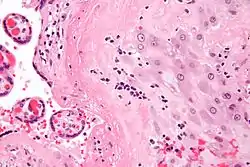

Micrograph of a chronic deciduitis, showing the characteristic plasma cells. H&E stain.

Chronic deciduitis is a type of long-lasting inflammation that arises in pregnancy and affects the endometrial stromal tissue (decidua).

It is associated with preterm labour.[1] The diagnosis rests primarily on the presence of plasma cells.[2]